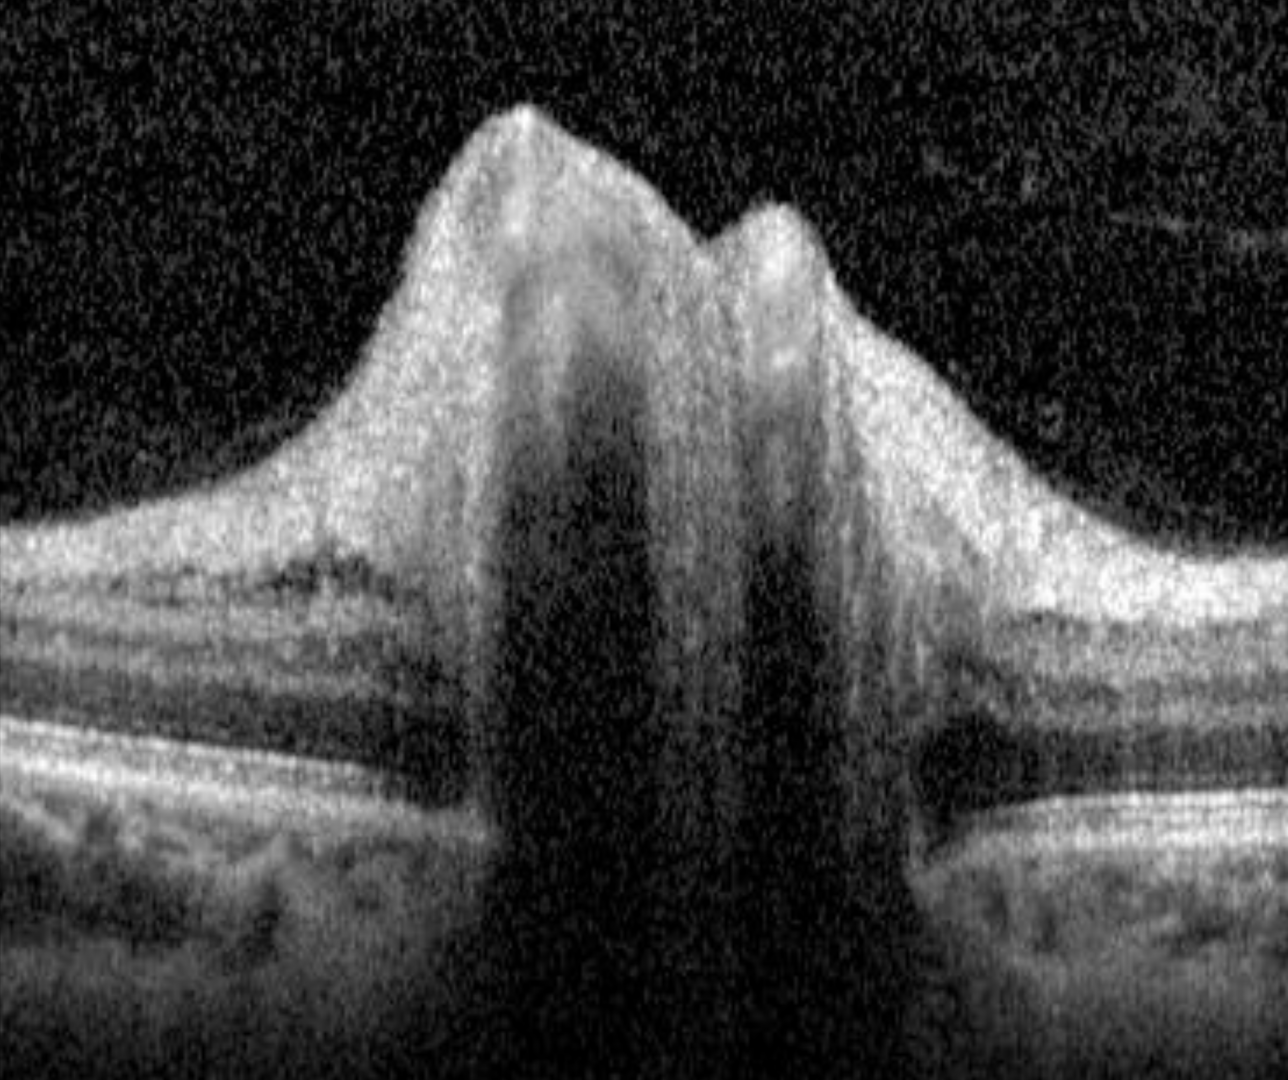

Diabetic papillopathy is a diagnosis of exclusion for patients with type 1 or type 2 diabetes who have disc oedema. It typically presents bilaterally with only a minimal disturbance to vision (if any) and a hyperaemic swelling of the optic nerve. A relative afferent pupillary defect is often not present and if it is, it is only mild. Mild vascular changes around the optic nerve head (as well as in the fundus) may be noted including venous engorgement with radially oriented disc telangiectasias and it may occur at any age in people with diabetes.